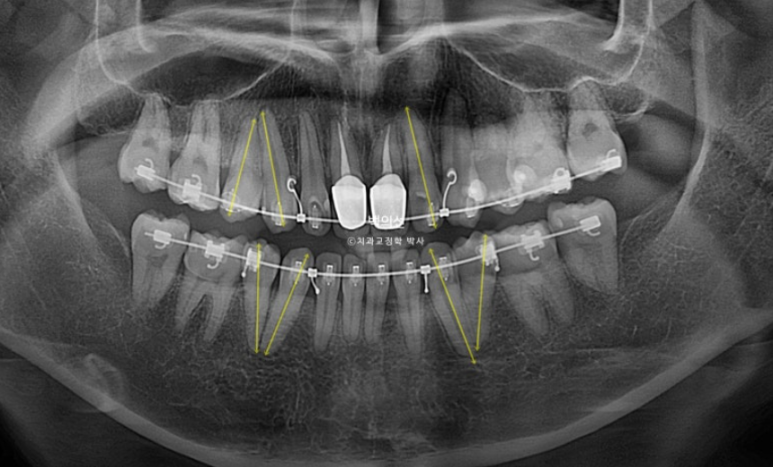

그런데 엑스레이상 치아 뿌리의 평행이 맞지 않는 부분들이 보입니다.

뿌리가 맞닿아 있으면 발치공간이 잘 닫히지 않을뿐더러 여러모로 좋지 않습니다.

치아 뿌리는 안 보이는 부분이지만 평행하게 맞추는 것이 장기적으로 환자분께 좋습니다.

환자분은 교정중이던 치과에 MRI촬영으로 인하여 인해 인비절라인으로 교정 방법을 바꿔 마무리 해주길 요청했었으나 기존치과에서는 인비절라인으로 뿌리이동이 안되기 때문에 발치교정은 절대 안된다. 라고

아까 엑스레이에서 치축이 기울어져 있던 파란화살표 측절치는 튀어나와 보이고 기울어져 보입니다.

뼈속에서 붙어있던 송곳니와 작은어금니 뿌리들은 4개월의 교정으로 비로소 서로 멀어지며 정렬을 찾았습니다.